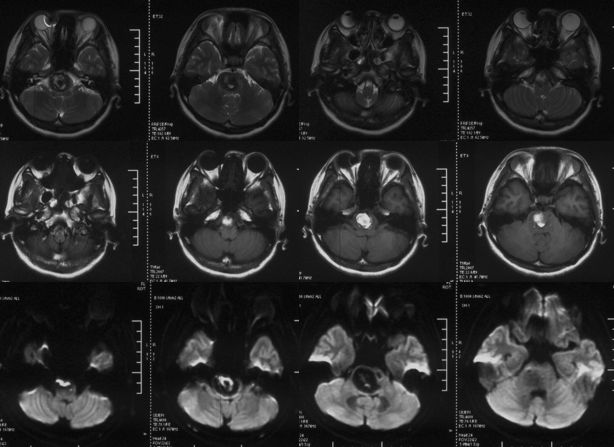

当地医院MRI:基底动脉中上段夹层动脉瘤(2019-09-16)(图4)。

图4

当地医院MRA:基底动脉中上段夹层动脉瘤(2019-09-16)(图5)。

图5

2、头部核磁共振显示:脑干占位性病变,边界较清晰,较大层面大小约35 mmx25 mm。MRA显示:基底动脉夹层动脉瘤。DSA显示,基底动脉巨大夹层动脉瘤,最大长径为:10.8 mm,最大短径为3.2 mm。根据患者症状及影像学诊断,基底动脉巨大夹层动脉瘤进行性增大压迫脑干,不排除脑干水肿可能,亟待手术治疗。